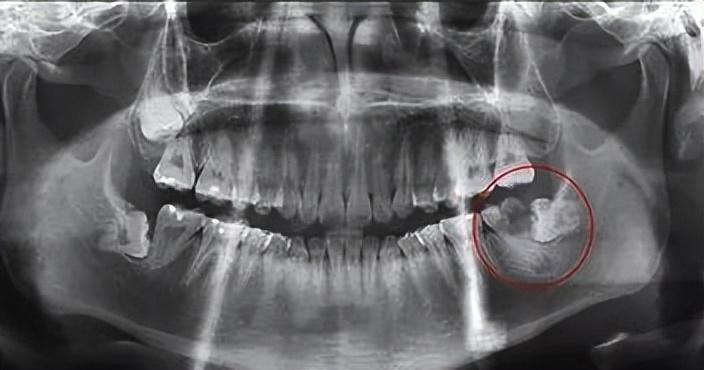

牙片出來(lái)后,長(zhǎng)這樣:

醫(yī)生看完牙片告訴我,牙齒中間黑色的部分是髓腔,外面白色的部分就是牙體,可以通過(guò)牙片看到牙齒的損壞情況。

很不幸,我靠近智齒的那顆牙也壞掉了。醫(yī)生說(shuō)是受到了智齒的擠壓,再加上位置較深,平時(shí)沒(méi)有做好清潔,所以齲壞了,目前齲壞程度較深,而且伴隨根尖炎,保留價(jià)值很低,建議拔掉后再種。